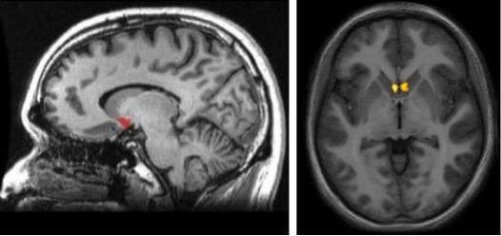

Now you might be asking yourself where this brain structure is located. In order to conceptualize it, visualize the subcortical (under the cortex) area right at the connecting point between the caudate nucleus, the putamen, and the septum. One of the most significant aspects of the nucleus accumbens is its location, as it’s a part of a dopaminergic pathway of the brain. This is the so-called mesolimbic pathway. It’s in charge of stimulating you whenever your brain believes you’re undergoing pleasurable and gratifying experiences.